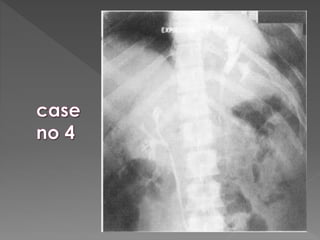

1) Pre contrast film “scout” film. (full length)

2) Immediately post contrast film. (Cross

kidney)